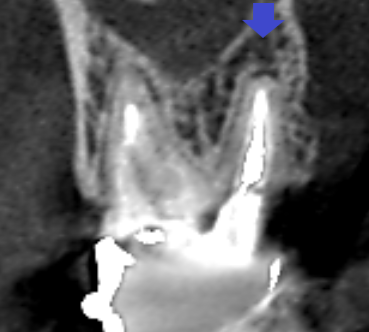

上顎第二大臼歯の冠状断のCT画像です。

矢印の上顎第二大臼歯の口蓋根の先に膿の影がみられます。根の先まで根管充填が届いていないのが分かります。